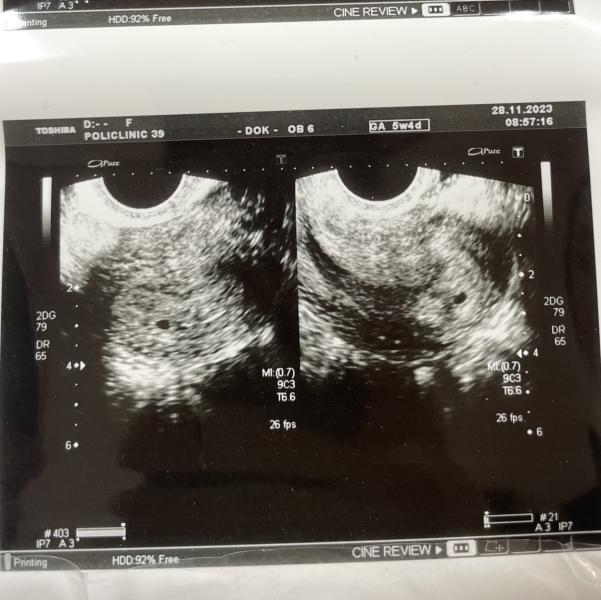

Сегодня первый раз ходила на узи👼🥰

28.11.2023